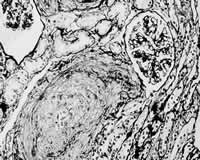

入院当日,患者尿量1750 mk,尿沉渣镜检:红细胞8~10 个/高倍视野,正常形态100 %;24 h尿蛋白定量0.39 g(参考值:<0.15 g)。予甲泼尼龙1 g/d×3日静点,继以泼尼松60 mg/d口服。冲击治疗次日,患者腹痛缓解,但尿量仅300 mk,血钾6.78 mmok/L,遂行血液透析。冲击治疗结束当日,患者无诱因再次出现腹痛,尿色呈洗肉水样,体温最高39.2 ℃。腹痛为上腹部两侧持续性绞窄性剧烈疼痛,无放射,不伴尿急、尿痛、呕吐、腹泻。查体:腹膜刺激征阴性,肠鸣音存在,双肾区叩痛阳性。实验室检查:血小板(PLT)计数下降,(116×109 /L→47×109 /L);激活的部分凝血活酶时间(APTT)58.4 s(参考值:28~42 s);血浆鱼精蛋白副凝试验阴性(参考值:阴性),优球蛋白溶解时间>90 s(参考值:<90 s)。腹部平片和B超未见异常;双肾动、静脉及肠系膜上动脉彩超未见异常。因观察到患者腹痛在血液透析开始后1 h左右明显减轻,而在血液透析结束后数小时又加重,故推测腹痛减轻与血液透析中应用肝素有关,遂于5月1日起予低分子肝素钙(速避凝)0.1 mg/d皮下注射。抗凝治疗2天后,患者腹痛缓解,体温正常,血小板计数、APTT逐渐恢复正常。住院期间,相隔8周两次查狼疮抗凝物(LA)阳性(参考值:阴性),抗心磷脂抗体(ACL)阴性(参考值:阴性)。5月30日,在全麻下行开放性肾活检术,病理结果:光镜下可见肾小动脉多数血栓形成,内膜呈葱皮样增厚,管腔狭窄及闭塞,多数肾小球呈缺血性皱缩,部分呈缺血性硬化;免疫荧光全部阴性(图1,图2)。住院期间,患者肾功能无恢复,予泼尼松60 mg/d 12周后逐渐减量),2001年8月出院。

图1 肾小动脉血栓形成,管腔几乎闭塞;肾小球呈缺血性皱缩改变。(HE染色,×200)

图2 肾小动脉血栓形成,内膜呈葱皮样增厚,管腔严重狭窄。(PAS-M染色,×200)